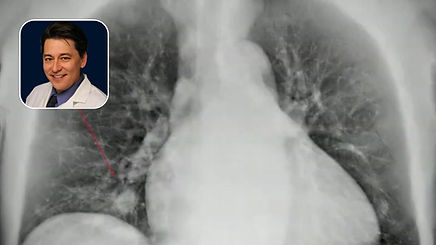

A patient presents to the ER with hemoptysis. When is bronchial artery embolization (BAE) the right call, and what can you do to tip the odds of procedural success in your favor? In this episode of the BackTable Podcast, interventional radiologist Dr. Alexander Lam of UCSF shares his approach to bronchial artery embolization with host Dr. Ally Baheti.